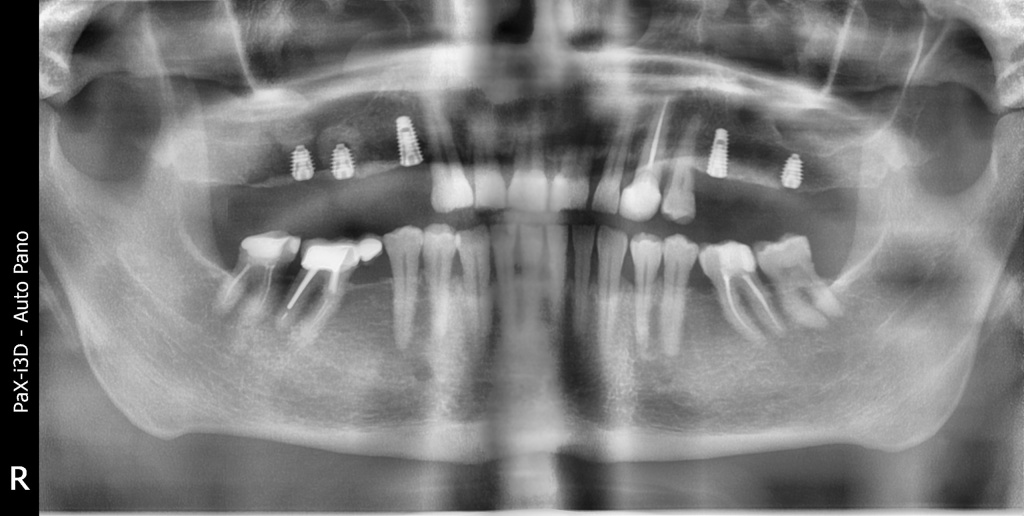

Плановая имплантация в жевательном отделе перед тотальной реабилитацией с поднятием прикуса.

Осложнения: сахарный диабет

По результатам диагностики принято решение установить имплантаты AnyRidge и AnyOne с использованием хирургических шаблонов Bonepen 3D.